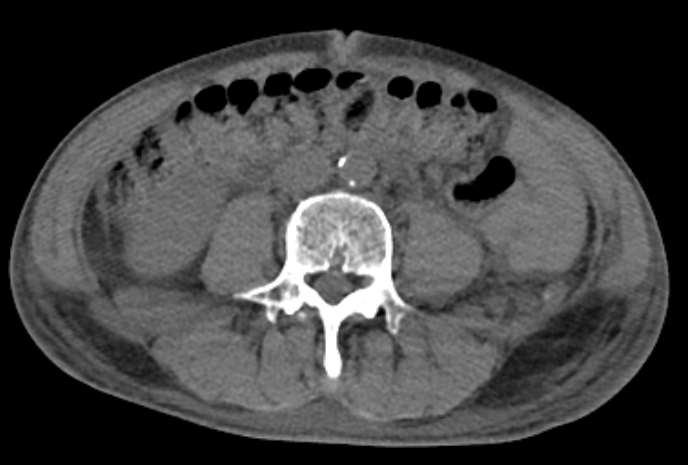

| CT | 장벽 비후, 염증 확산, 청공 여부 확인 |